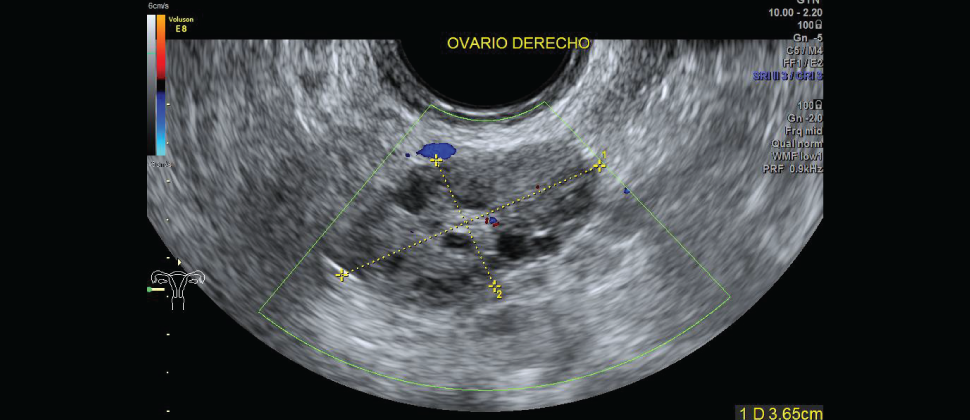

Es un procedimiento de ultrasonido transvaginal, generalmente se realiza primero para observar el endometrio, o las paredes del útero, incluyendo su grosor y toda anormalidad ovárica relacionada.

Muchas anormalidades uterinas que no se pueden observar de manera adecuada con un ultrasonido transvaginal de rutina se pueden observar en detalle con la histerosonografía.

Se pueden observar en detalle con esta prueba, por ejemplo los pólipos endometriales o los miomas submucosos o el endometrio en mujeres con cáncer de mama en tratamiento con Tamoxifeno.